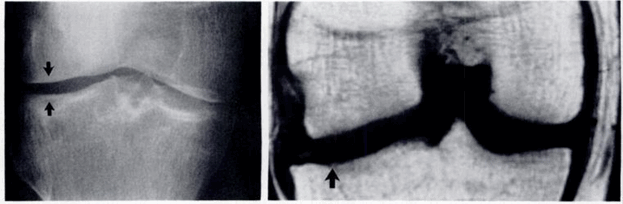

(Слева) Рентгенография в ПЗ проекции: истончение хряща в медиальном отделе коленного сустава и крупный субхондральный остеофит с минимальными краевыми остеофитами.

(Справа) МРТ, сагиттальная проекция, режим Т2 с подавлением сигнала от жира: срез выполнен несколько медиальнее субхондрального остеофита, однако здесь определяется обширный дефект хряща нагружаемой зоны медиального мыщелка бедренной кости, наряду с признаками расслоения. Сигнал от субхондральных остеофитов достоверно ассоциируется с повреждением хряща. (Слева) МР-артрография, сагиттальная проекция, режим Т2 с подавлением сигнала от жира: определяется обширный дефект хряща в области блока, а также признаки отека костного мозга. Необходимо скрупулезно исследовать область блока, оценка протяженности повреждения которого может быть затруднена, поскольку его поверхность обычно не ортогональна плоскости исследования.

Потерю хряща на рентгенограмме оценивали с помощью измерения ширины суставной щели. На МРТ непосредственно измеряли высоту суставного хряща. Потеря хряща на рентгенограмме была выявлена в медиальном отделе в 57(85 %), в латеральном отделе в 23(34.3 %), на МРТ в 63(94 %) и 40(59.7 %) суставах соответственно.

Остеофиты на рентгенограмме и на МРТ выявляли как краевые приострения суставных поверхностей костей(рис.1). Остеофиты на рентгенограмме были выявлены в медиальном и латеральном отделах в 40(59.7 %), на МРТ в 67(100 %) и 57(85 %) суставах соответственно.

На рентгенограммах субхондральные кисты проявлялись округлой формы участками просветления. На МРТ в режиме Т2 они определялись как участки гиперинтенсивного сигнала на фоне нормального гипоинтенсивного костного мозга (рис.2). Субхондральные кисты на рентгенограмме были выявлены в медиальном отделе в 13(19.4 %), на МРТ в медиальном отделе в 27(40.3 %), в латеральном отделе 13(19.4 %) суставах.

Рис. 1. Рентгенограмма и МРТ коленных суставов больной З.,62 лет. На рентгенограмме (А) выраженное сужение медиальных отделов суставной щели, краевые остеофиты, субхондральный склероз. На МРТ(Б) краевые приострения, выраженные дегегнеративные изменения в медиальных отделов субхондральной кости, выраженное истончение медиального отдела хряща. Дегенерация медиального мениска

Рис.2. Рентгенограмма и МРТ больной Б., 55 лет. А) Рентгенограмма не показывает признаки образования субхондральных кист. Б) МРТ (Т2) показывает кисту с высоким сигналом. Его легко можно дифференцировать от окружающего нормального костного мозга с низким сигналом

Вследствие нарушения равновесия между образованием нового строительного материала для восстановления хряща и его разрушением, хрящ истончается, на нем появляются язвы, обычно только в наиболее нагружаемой части сустава [5]. МРТ в сравнении рентгенографией более чувствительна в выявлении истончения хряща в латеральном отделе коленного сустава. На МРТ обнаруживалось истончение суставного хряща в латеральных отделах сустава, которые на рентгенограмме не проявлялись изменением суставной щели. Так как большая часть нагрузки приходится в медиальные отделы коленного сустава, изменения суставного хряща начинается с этой части сустава. На рентгенограммах в первую очередь суживается медиальные отделы суставной щели. При этом латеральные отделы суставной щели остаются не измененными и даже несколько расширяются. Это приводит к ложному выводу о интактности суставного хряща в этом отделе, изменения которого достоверно выявляется на МРТ (см.рис.3). Этим можно объяснить более низкую встречаемость изменения суставного хряща в латеральном отделе коленного сустава на рентгенограммах (23 суставах).

Рис.3. Рентгенограмма и МРТ больной Ш.,58 лет. А) Рентгенограмма показывает умеренное расширение латерального отдела суставной щели. Б)

МРТ показывает истончение хряща в этом же отделе

Субхондральные кисты возникают за счет фокальной эрозии кости в местах повышенного внутрисуставного давления, что чаще связано с истончением суставного хряща. В обоих методах исследования субхондральные кисты больше выявлялись в медиальном отделе сустава. Оценка наличие субхондральных кист с помощью рентгенографии была сложной при наличии остеопороза и на фоне грубого трабекулярного рисунка субхондральной кости (13 суставах). Мелкие субхондральные кисты лучше выявлялись на МРТ благодаря срезам в различных плоскостях. На МРТ субхондральные кисты лучше выявлялись в режиме Т2 STIR в виде повышения интенсивности сигнала (рис3).

Краевые приострения суставных концов являются результатом компенсаторной реакции в ответ на изменения нормального распределения физической нагрузки на суставные поверхности из-за истончения суставного хряща. Остеофиты самый частый выявляемый признак остеоартроза на рентгенограммах и МРТ. В некоторых случаях на рентгенограммах возникает сложность выявления небольших остеофитов за счет суммационного эффекта рентгеновских изображений. В группе нашего исследования остеофиты не были выявлены в 27 (40.2 %) суставах в медиальных и в 27 (40.2 %) латеральных отделах на рентгенограммах. Из них на МРТ наличие остеофитов выявлено в медиальном и латеральном отделах в 27 и 17 соответственно. Остеофиты чаще встречались и были более выраженными в медиальном отделе суставного конца бедренной кости. Это даёт основание считать что, образование остеофитов начинается в этой части коленного сустава. Мелкие остеофиты в этом отделе коленного сустава трудно выявлять на рентгенограммах. Чувствительность МРТ в этом отношении намного больше рентгенографии, благодаря возможности получения томографических изображений, с минимальной толщиной срезов, в различных плоскостях. Но рентгенография оказалась более информативным при оценке наличия остеофитов в пателло-феморальном сочленении. Остеофиты чаще встречались в верхнем и нижнем концах надколенника. За счет отсутствия сигнала от кортикального слоя кости на сагиттальных МР срезах небольшие краевые приострения не всегда удается выявлять с помощью МРТ.